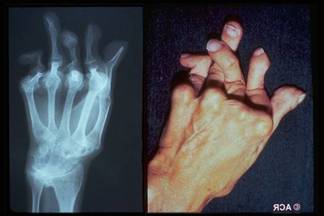

Artrite reumatoide

È una malattia sistemica del connettivo ad elettiva localizzazione poliarticolare, ad andamento cronico e progressivo, con carattere erosivo, a tendenza anchilosante, caratterizzata dalla presenza sierica di anticorpi anti-immunoglobuline denominati fattori reumatoidi.

Precoce interessamento di mani e piedi: deformazione a collo di cigno, a boutonniere, dita a martello, mani a colpo di vento;

Deformità articolari;

Alterazioni radiologiche (osteoporosi distrettuale ed erosioni alle radiografie di mani e polsi

Segni radiologici

1) Precoci:

Tumefazione dei tessuti molli

Osteoporosi periarticolare

Periostite

Erosioni dei margini articolari

Cisti subarticolari

2) Avanzati:

Rime articolari ristrette

Irregolarità delle superfici articolari

Sublussazioni articolari

Osteoporosi generalizzata

Alterazioni degenerative secondarie

Anchilosi ossea